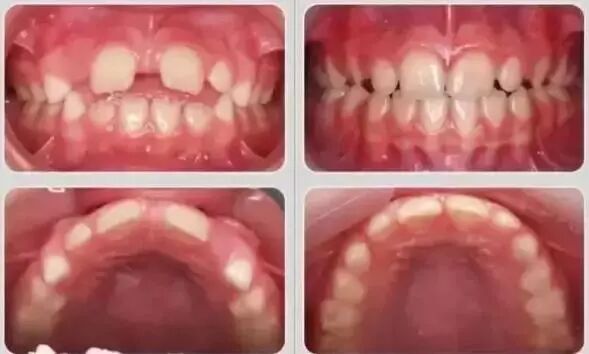

乳牙期效果对比